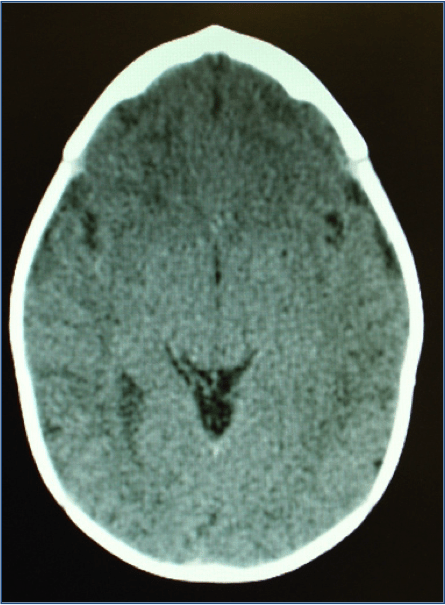

Craniosynostosis refers to a premature closure of cranial suture(s). Its incidence ranges from 1/1,800 to 1/2,500 live births. I can either be isolated or involve multiple suture. It is also classified as Non-syndromic vs. Syndromic.

Visit your Craniofacial Surgeon if you have any question with regards to the shape of your baby’s head. Craniosynostosis can be misdiagnosed for positional plagiocephaly. The diagnosis is a clinical one. No imaging is usually necessary to make a diagnosis.